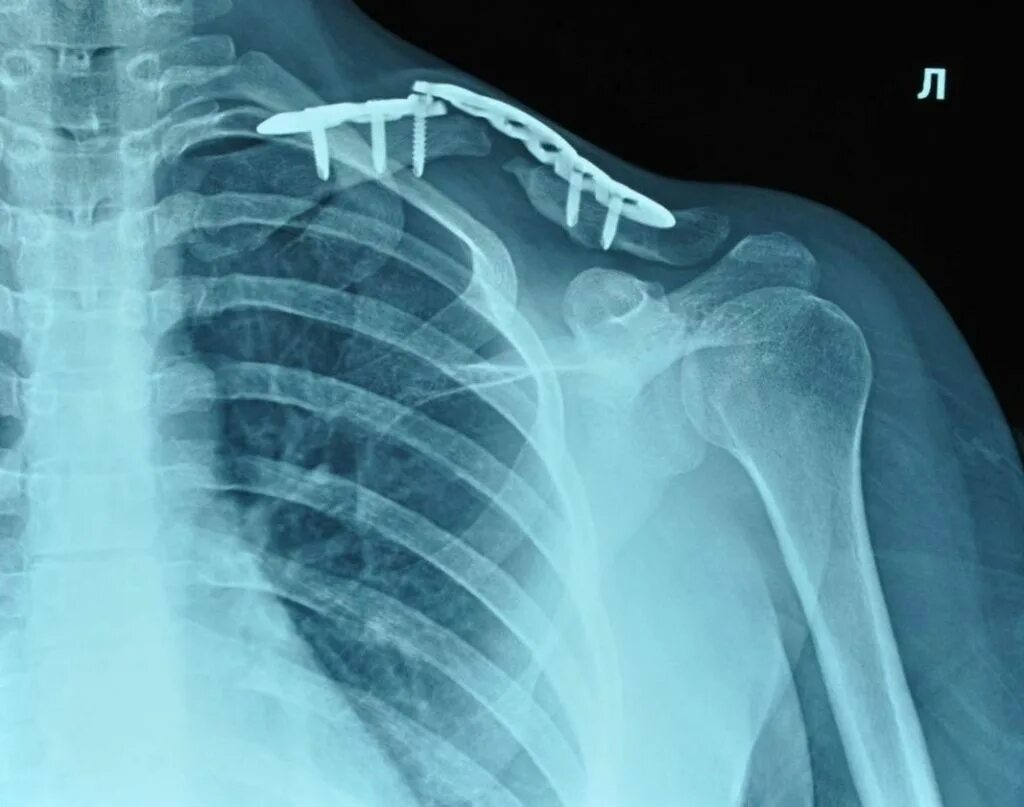

Хрустит ключица